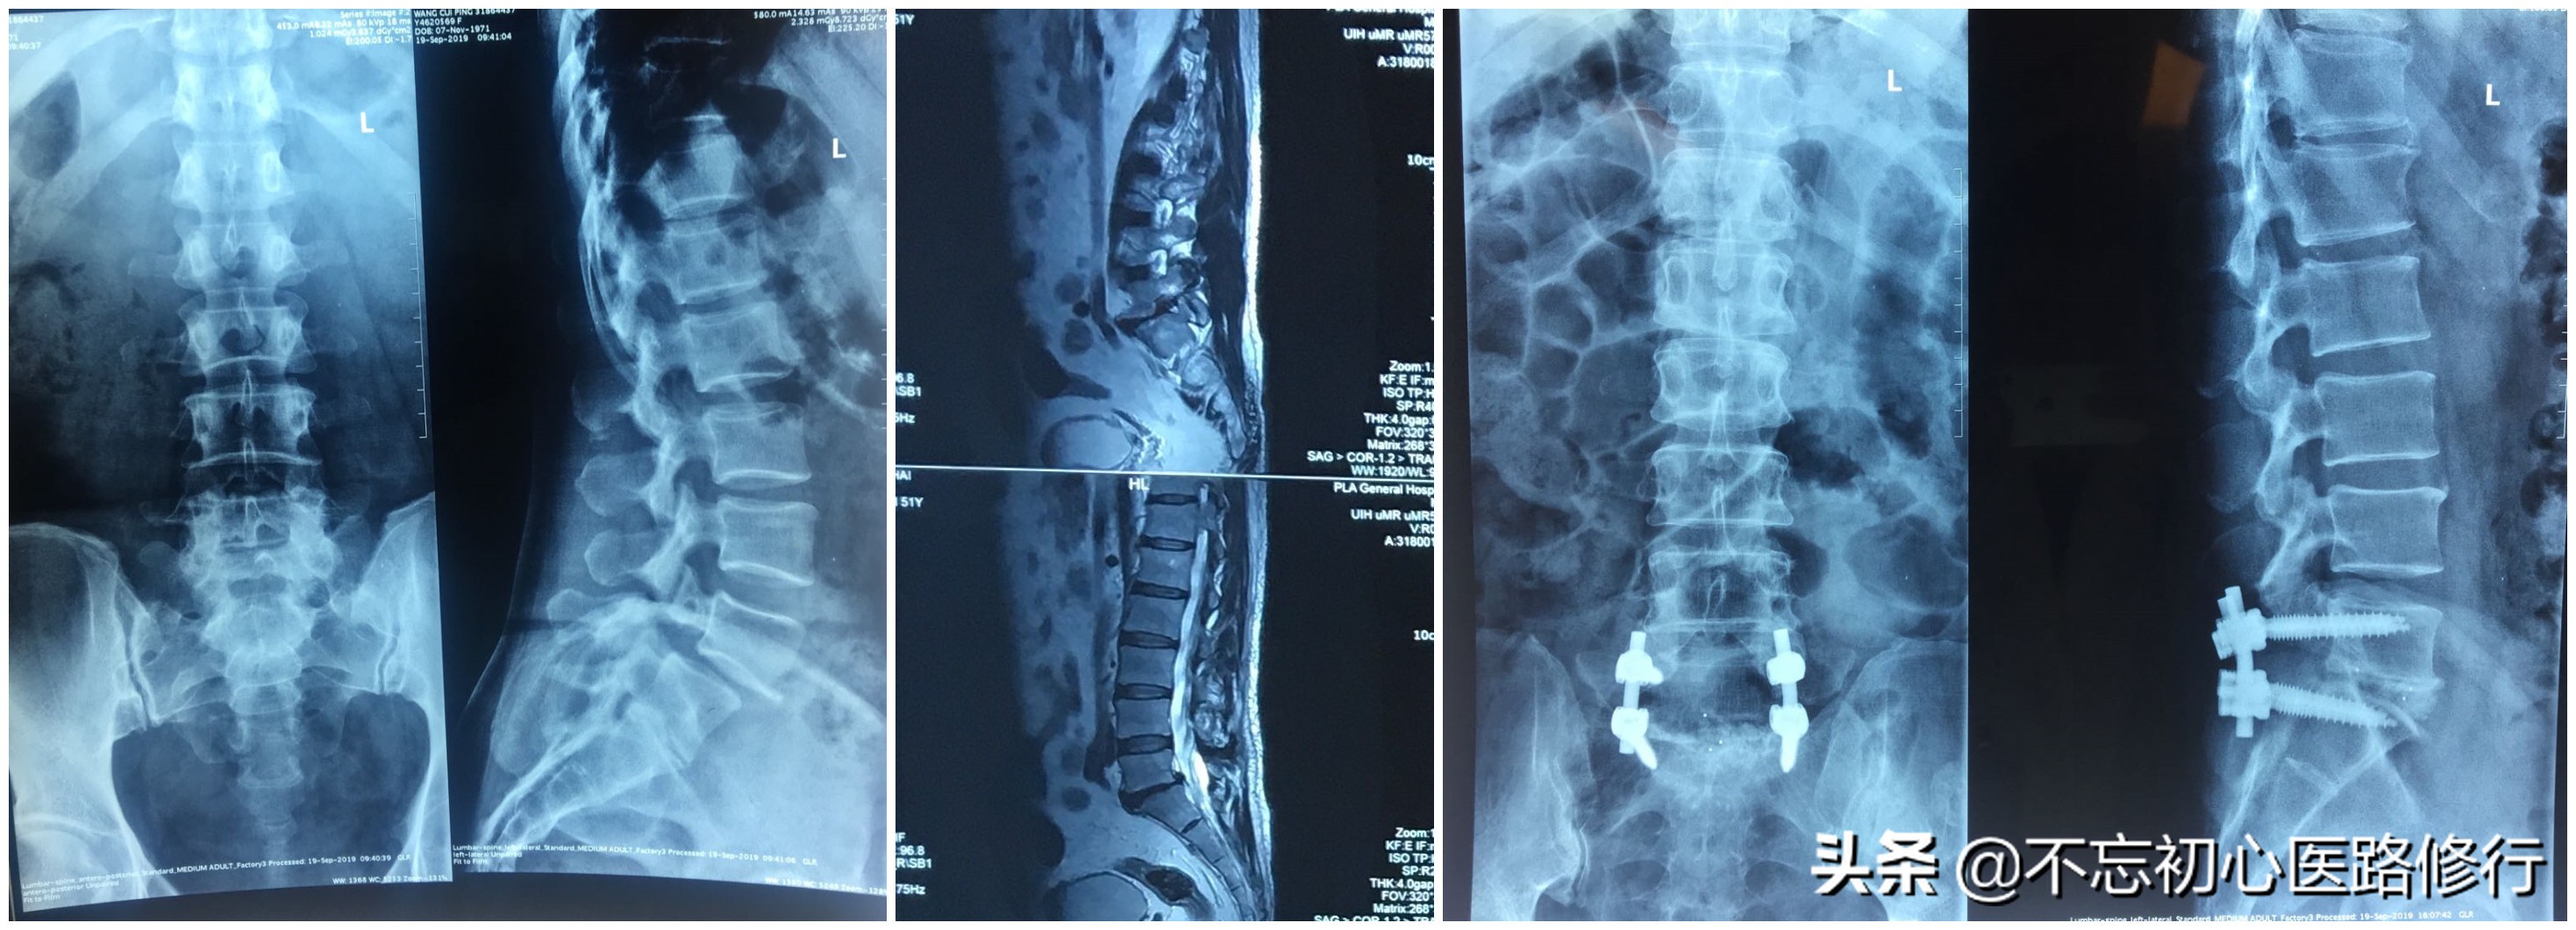

二、手术治疗。

适应症:1)腰腿疼痛症状严重,反复发作,经过半年以上的保守治疗无效,病情逐渐加重,影响工作和生活的;2)伴有马尾综合征的,要急诊手术;3)有明显神经受累的表现的。

1、微创手术:手术在椎间孔镜下完成,创伤小,恢复快。

2、开放减压植骨融合手术: